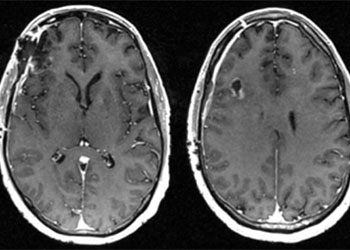

Brain:

Cerebral Metastases from Non-Small Cell Lung Cancer

Author: Xavier P. J. Gaudin D.O., F.A.C.O.S., Read More!